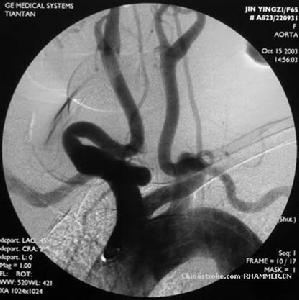

腦血管造影可以發現頸內動脈 起始部、大腦 前、中動脈起始段狹窄或不顯影,基底節區可見大量細小血管團如吸菸吐出的煙霧。此外可見腦內形成側支循環代償支。隨著病程的延長,代償吻合支的數量逐漸減少或縮小。

5、腦血管造影:見頸內動脈虹吸上段和大腦前、中動脈起始部狹窄,腦底煙霧狀異常血管網和廣泛的側支循環形成。應與腦動脈硬化性腦梗死和動靜脈畸形 鑑別。